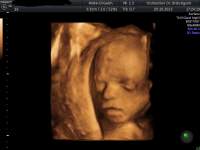

Ultraschall

Routinemäßig wird bei jeder Mutterkindpaßuntersuchung ein Ultraschall durchgeführt.

So kann einerseits am Anfang der Schwangerschaft der Geburtstermin bestätigt oder bei Unklarheit bestimmt werden, andererseits können durch eine kontinuierliche Betreuung viele etwaige Gefahren für die Schwangerschaft frühzeitig erkannt werden.

Deshalb führe ich je nach Schwangerschaftswoche ergänzend Durchblutungsmessungen der Gebärmutterarterie (Arteria uterina) oder der Nabelschnurarterie (Arteria umbilicalis) durch.

Diese dienen dazu den Versorgungszustand zu überprüfen bzw. eine etwaige Gefährdung ihres Babys frühzeitig zu erkennen.

Je nach dem Ergebnis werden dann die nächsten Kontrollen vereinbart.